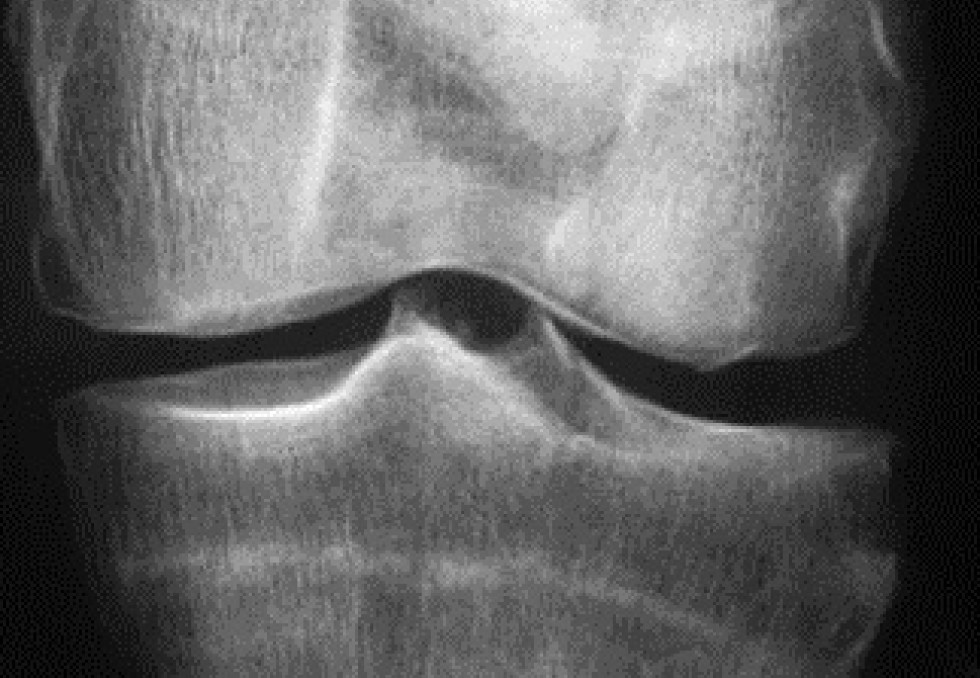

[CONGRES DE L'EULAR] Le congrès de la Ligue européenne contre les rhumatismes (Eular), qui s’est déroulé à Madrid du 12 au 15 juin 2019, a confirmé que, dans l’arthrose, la recherche de traitements se poursuit, alors que le nombre de médicaments disponibles se réduit. Divers agents modifiant le métabolisme osseux ou cartilagineux, limitant la douleur ou l’inflammation, sont en développement.   Trouver de nouvelles solutions thérapeutiques est indispensable dans l’arthrose. La maladie connait en effet un développement considérable dans le monde, ce qui est source d’une charge croissante pour la société. En outre, il s’agit d’une maladie sérieuse qui s’associe à un excès de mortalité, notamment cardiovasculaire en comparaison de la population générale, a rappelé le Pr Francis Berenbaum (Hôpital Saint-Antoine, AP-HP, Paris). Une étude américaine conduite à partir d’analyses de squelettes a, par exemple, observé que 8 % des individus de plus de 50 ans présentaient des signes de gonarthrose à la période préhistorique (6000-300 before present), 6 % à la période pré-industrielle (1800-1900) et 16 % depuis la période post-industrielle (fin des années 1900 au début des années 2000) (1). "Ce doublement de prévalence de l’arthrose met probablement en cause d’autres facteurs liés à l’environnement que l’obésité et qu’il faudra identifier", a indiqué le Pr Berenbaum. Que faire ? En premier lieu, proposer les traitements non pharmacologiques tels qu’exercice, réduction du poids, aide à la marche au besoin avec des dispositifs techniques. Les recommandations de l’Eular (qui concernent aussi les patients avec une polyarthrite rhumatoïde (PR) ou un rhumatisme psoriasique) préconisent en cas de gonarthrose ou de coxarthrose la pratique d’exercices contribuant à améliorer santé cardiorespiratoire, force musculaire, souplesse et performances neuromotrices (2).   Peu de moyens médicamenteux Sur le plan médicamenteux, "les moyens disponibles sont de moins en moins nombreux", a admis le Pr Berenbaum.  De fait, une méta-analyse Cochrane (10 essais randomisés, 3541 patients), publiée en février 2019, a conclu que l’efficacité antalgique et fonctionnelle du paracétamol (pourtant conseillé en 1e ligne dans toutes les recommandations internationales) est faible (3). Une étude danoise réalisée à partir de 252 études de cohorte nationales a aussi suggéré que les anti-inflammatoires non stéroïdiens oraux (préconisés en 2e ligne) exposent non seulement à un risque cardiovasculaire accru au long cours, comme on le suspectait depuis longtemps, mais que le diclofénac pourrait majorer de 20 à 80 % à court terme la probabilité de survenue d’événements cardiovasculaires (4). En septembre 2018, l’ANSM a d’ailleurs rappelé aux prescripteurs français d’AINS la nécessité "d’évaluer au préalable les risques cardiovasculaires du patient" et "d’administrer les doses les plus faibles possibles et pour la durée la plus courte possible". En mars 2019, c’est le tramadol qui était à son tour visé avec la publication d’une étude décrivant un excès de mortalité (en comparaison des AINS) chez les patients arthrosiques de plus de 50 ans ayant pris cet antalgique (5). Dans ce contexte décourageant, "les améliorations ne peuvent venir que de l’innovation", a considéré le Pr Berenbaum. Fort heureusement, quelques cibles d’action ont été identifiées qui reposent sur le freinage du catabolisme osseux (voie WNT, cathepsine K), ou cartilagineux (inhibiteurs de métalloprotéases), l’activation de l’anabolisme ou la régénération du cartilage. "Pour le moment, agir sur l’inflammation en inhibant l’interleukine 1 a été un échec mais la cytokine ciblée n’était peut-être pas la bonne." Un essai de phase 2 b de 24 semaines, présenté en octobre 2018 par le Dr Yusuf Yazici (San Diego, États-Unis), lors du congrès de l’American College of Rheumatology, a rapporté des résultats intéressants sur le plan fonctionnel dans la gonarthrose, après injections intra-articulaires de lorecivivint, un inhibiteur de la voie WNT impliquée dans le catabolisme osseux. Le MIV-711, un inhibiteur sélectif de la cathepsine K, semble aussi prometteur. Le développement de la sprifermine est, quant à lui, "plus avancé". Cette molécule, qui active la production de cartilage par les chondrocytes en activant les récepteurs du fibroblast growth factor (FGF), a montré dans des résultats préliminaires de l’essai de phase 2 de 2 ans Forward, un effet structural dans la gonarthrose. La médecine régénérative, qui fait le buzz sur la toile, se développe aussi avec les injections de cellules mésenchymateuses, dont on espère qu’elles auront la capacité de se transformer en chondrocytes fabriquant du cartilage ou de sécréter des molécules anti-inflammatoires ou freinant les processus de dégradation osseuse. Une méta-analyse a conclu à la sécurité de cette stratégie thérapeutique et à ses effets positifs pour améliorer à 1 an scores de douleur et de fonction articulaire dans la gonarthrose (6). "Mais cela reste à vérifier dans un essai randomisé rigoureux", a insisté le Pr Berenbaum. C’est d’ailleurs l’objectif de l’étude Adipoa-2, qui va comparer en double aveugle chez 153 patients, suivis 25 mois, injection dans le genou de cellules mésenchymateuses (à 2 doses) et placebo.   Une biothérapie antalgique Enfin, la lutte contre la douleur reste essentielle dans l’arthrose ; "20 % des patients avec une prothèse de genou continuent de se plaindre de douleurs chroniques". Le nerve growth factor (NGF), une neurotrophine qui intervient dans la transduction du signal douloureux semble être une bonne cible. L’analyse de plusieurs études cliniques de phase 3 contrôlées contre placebo, menées dans la gonarthrose ou la coxarthrose, vient de confirmer que le tanézumab, un anticorps monoclonal humanisé dirigé contre le NGF, a une efficacité intéressante contre la douleur arthrosique (8). Cependant, étant donné un risque certes faible mais significatif d’arthrose rapidement progressive (1 à 3% des patients traités), liée probablement au fait que les patients ne ressentent plus la douleur, "la question sera de savoir à quels patients proposer en priorité cette biothérapie, que l’on administre sous la forme d’injections sous-cutanées toutes les 8 semaines".     1 - Wallace IJ, et al. Proc Natl Acad Sci U S A. 2017;114:9332-9336. 2 - Rausch Osthoff A.K, et al. 2018 EULAR recommendations for physical activity in people with inflammatory arthritis and osteoarthritis. Ann Rheum Dis. 2018;77: 1251-1260. 3 - Leopoldino AO, et al. Cochrane Database of Systematic Reviews 2019, Issue 2. Art. No.: CD013273. 4 - Schmidt M, et al. BMJ 2018;362:k3426. 5 - Zeng C, et al. JAMA. 2019;321:969-982. 6 - Yubo M, et al. PLos One 2017.12(4): e0175449. 7- Tive L, et al. J Pain Res. 2019;12:975-995.